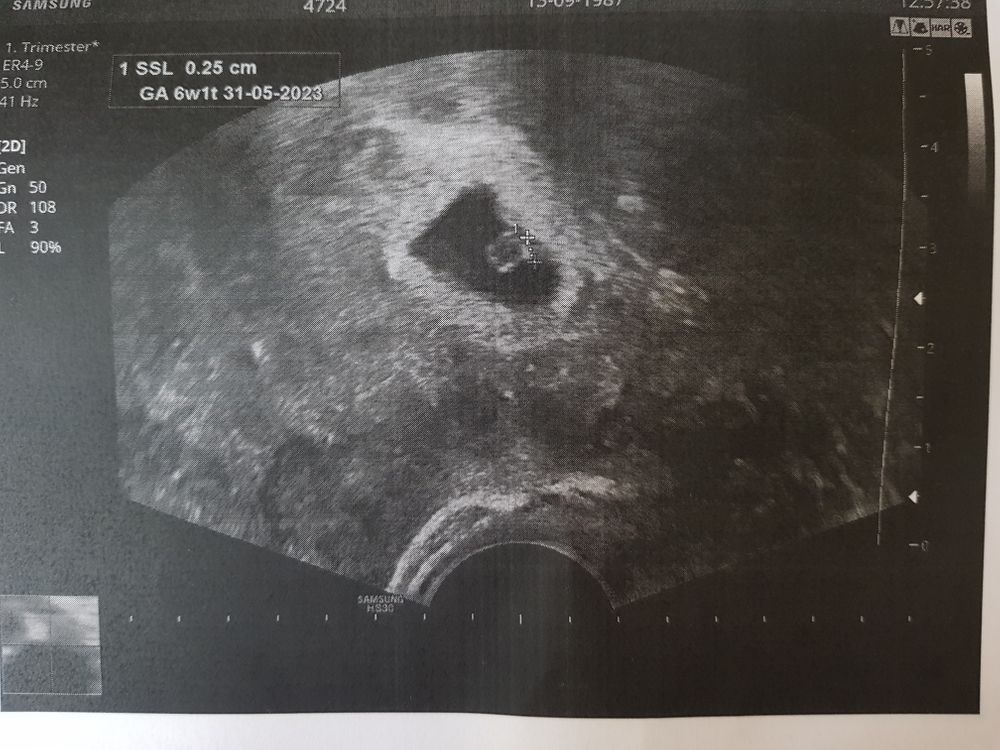

Была сегодня на узи. И уже есть сердцебиение)